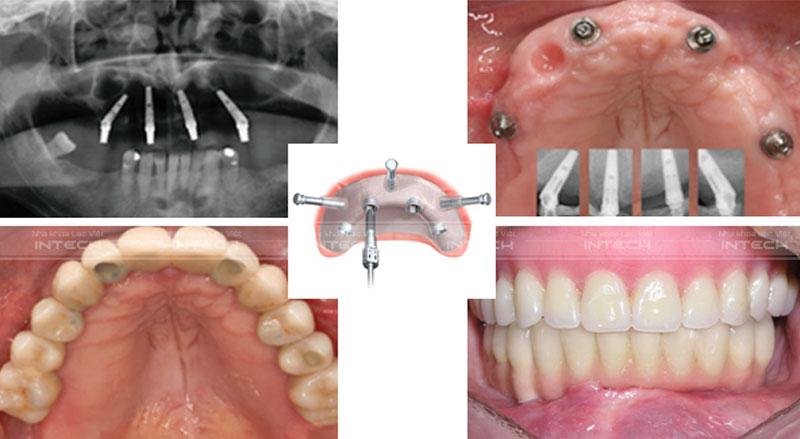

• Trồng răng implant all on 4 - Và all on 6: Bác sĩ sẽ cấy 4 hoặc 6 trụ implant vào trong xương hàm, sau đó sẽ hàm Hybrid bên bao gồm 12 hoặc 14 răng được kết nối với trụ implant bằng phương pháp bắt vít thông qua Mutiunit. Đây là phương pháp hiện đại nhất hiện nay và cũng có mức chi phí cao hơn các phương pháp cổ điển do yêu cầu  trang thiết bị hiện đại và phát sinh chi phí Mutitunit. Tuy nhiên, với ưu điểm vượt trội, đảm bảo sử dụng lâu dài, khôi phục khả năng ăn nhai và thẩm mỹ như răng thật, dễ dàng vệ sinh, dễ dàng xử lý các vấn đề phát sinh khác nên Hệ thống Nha Khoa Lạc Việt intech lựa chọn áp dụng cho 99% khách hàng mất răng toàn hàm, toàn hai hàm.

Trồng răng Implant toàn hàm All-on-4 được coi là giải pháp điều trị nha khoa mang tính cách mạng dành cho những bệnh nhân bị mất răng toàn hàm. Kỹ thuật trồng răng Implant All-on-4 được thực hiện bằng cách cấy 4 trụ Implant/ hàm. Trong đó có 2 trụ Implant được đặt thẳng tại vị trí răng số 2 và 2 trụ Implant được cấy với góc nghiêng tối đa lên tới 45 độ tại vị trí răng số 5. Cùng với đó là sự hỗ trợ của Multi-unit Abutment có khả năng liên kết và nâng đỡ 1 hàm giả gồm 12 chiếc răng sứ.

Tương tự như trồng răng Implant All-on-4, kỹ thuật trồng răng All-on-6 được thực hiện bằng cách cấy ghép 6 trụ Implant/ hàm. Tuy nhiên, điểm khác biệt đó chính là các trụ Implant đều được cấy thẳng, trong đó có 4 trụ giữa được cắm tại vị trí răng trước và 2 trụ ở hai bên được cắm ở vị trí răng hàm.

Trồng răng Implant All-on-6 có thể nâng đỡ hàm giả bao gồm 12 - 14 răng, đảm bảo độ chắc chắn và đem lại khả năng ăn nhai như răng thật. Tuy nhiên, phương pháp này có một nhược điểm là phải ghép xương trong một số trường hợp bệnh nhân bị tiêu xương quá nhiều do mất răng trong một thời gian dài.

Hình ảnh minh họa phương pháp all on 4

• Tiếp theo, sử dụng kỹ thuật phẫu tích vi phẫu không cần rạch vạt lợi, xâm lấn tối thiểu để đặt chân răng Implant. Tùy theo phương pháp trồng răng All-on-4 hay All-on-6, bác sĩ sẽ đặt 4 hoặc 6 trụ Implant theo kế hoạch điều trị ban đầu.

• Sau khi cấy ghép Implant, các Multi-Unit Abutment sẽ được gắn cố định luôn vào Implant, đóng vai trò chuyển tiếp từ chân Implant đến hàm Hybrid.

Bước 3: Lắp hàm Hybrid sau cùng

Sau khi Implant đã tích hợp ổn định với xương hàm, khách hàng sẽ được hẹn lịch đến lắp hàm Hybrid sau cùng. Hàm Hybrid sẽ được gắn chặt vào các trụ Implant thông qua vít kết nối. Sau khi lắp răng, bệnh nhân sẽ có một hàm răng mới đều đẹp, thẩm mỹ như răng thật và khôi phục 98% chức năng ăn nhai.